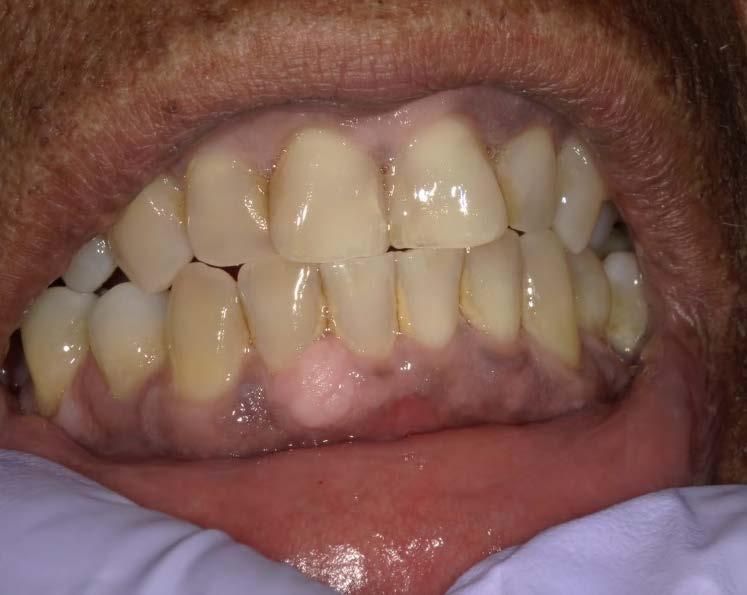

Technique for extracting tooth or root tip from underneath fixed partial denture emphasizes use of magnification from dental loupes or dental surgical operating microscope for precision when performing technique-sensitive procedure. Case report.